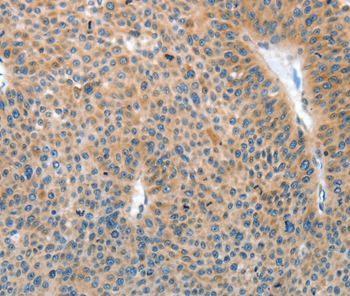

Immunohistochemical analysis of paraffin-embedded Human liver cancer tissue using #35608 at dilution 1/15.

Immunohistochemical analysis of paraffin-embedded Human lung cancer tissue using #35608 at dilution 1/15.